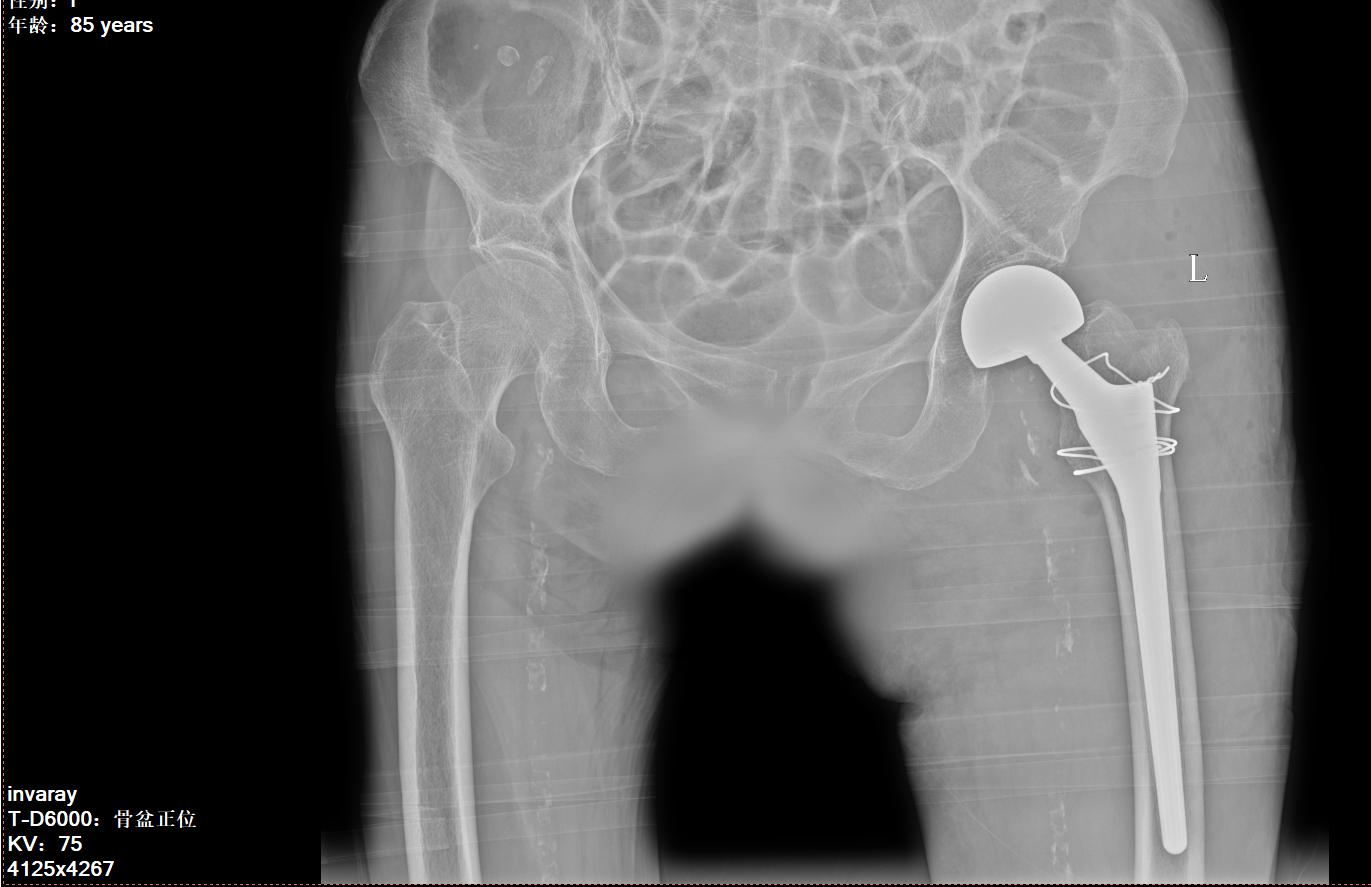

入院后,南区骨科团队对患者进行了全面评估。老人不仅患有左股骨粗隆间骨折,还合并高血压、贫血等基础疾病,手术风险较高。骨科专家团队迎难而上,经过详细检查,确认无绝对手术禁忌后,于10月3日在成功为老人实施了“左加长柄人工股骨头置换术”。

术后,骨科医护团队为患者制定了个性化的康复方案,包括止痛消肿、预防血栓、早期功能锻炼等。令人惊喜的是,术后第二天,老人在家人和医生的搀扶下,就能在助行器辅助下站立并行走!医护人员耐心指导她进行股四头肌收缩、踝泵运动等训练,有效预防了下肢深静脉血栓等并发症。复查X线显示,人工关节假体位置良好,骨折复位满意。经过两周的精心治疗和康复,黄女士的切口愈合良好,已能借助助行器独立行走,生活自理能力显著提升。